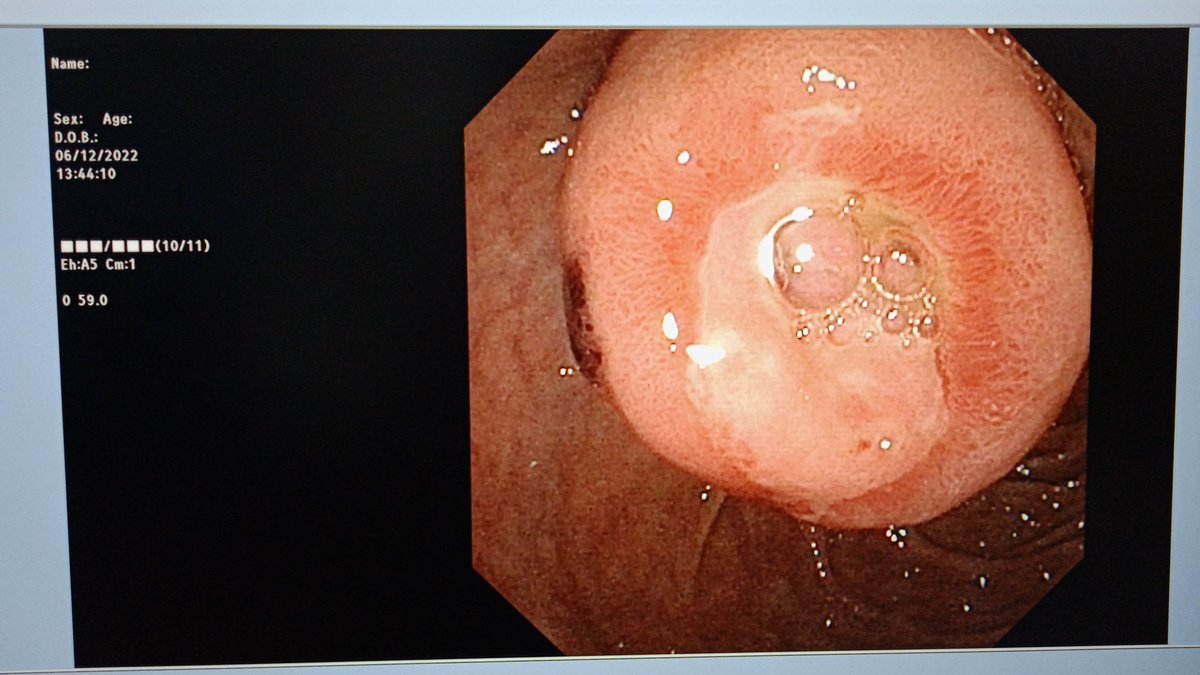

A case of ampullary NET Grade 1 on biopsy Eus/ct/mr suggest lesion limited to ampulla Ampullectomy done. The entire tumor was respected enbloc with intact surrounding capsule There was significant arterial bleeding- controlled with hemoclip application #AIIMSJodhpur